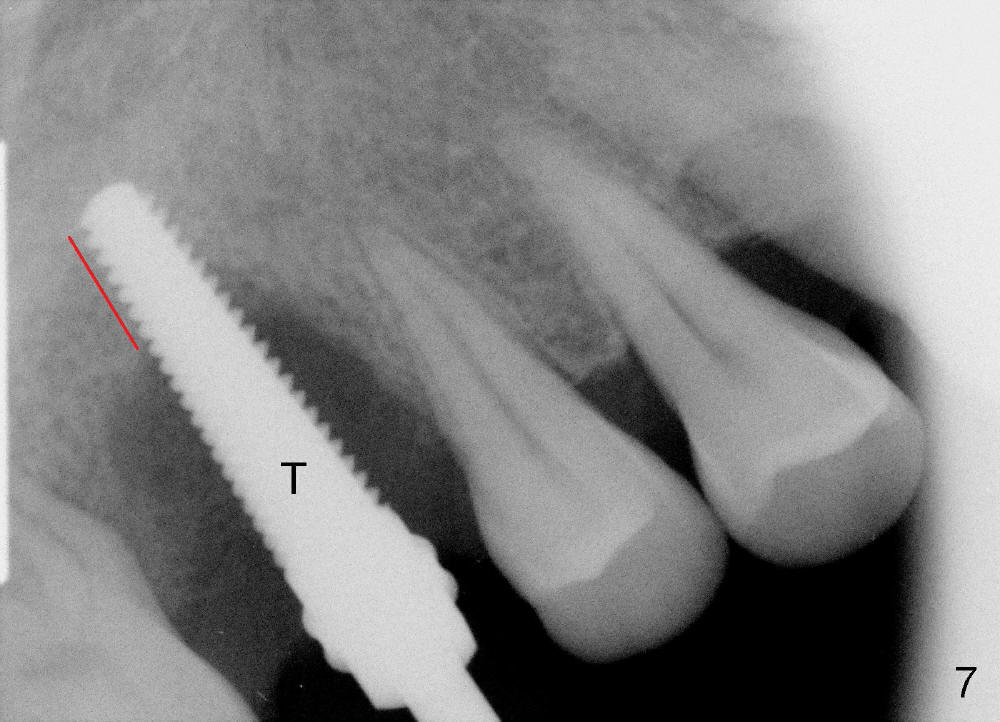

The tooth #3 has severe periodontitis with probably endodontic lesion (Fig.1,2). The patient is a 43-year-old man with apprehension of dentistry. An acute infection causes pain and tooth shift (Fig.4,5). A 7x17 mm immediate implant is planned (Fig.3). The palatal socket is shallow (Fig.6 P), corresponding to severe recessive palatal root (Fig.5 P). The osteotomy is created mainly in the buccal socket (Fig.6 B), exactly in the lingual slope of the septum. Initially osteotomes are used, followed by tap placement (Fig.7 T (4.5x20 mm at the depth of 17 mm). When the implant is placed as planned (Fig.8 I), there is more vertical contact (Fig.8 red line) than that associated with the tap (Fig.7 red line). The corresponding insertion torque is between 50 and 60 Ncm. There is only one small gap buccally, which is filled with bone graft (Fig.9 <). After the insertion of a short abutments with vertical slots (Fig.9,10 A), perio dressing is used to cover the wound. The palatal socket is expected to heal uneventfully (Fig.10 P). In fact, it does in 7 days (Fig.12 P); the bone graft in the mesiobuccal aspect is healing and stabilized (Fig.11 <). By two weeks postop, the mesiobuccal socket has healed (Fig.13 <). With removal of a diseased tooth, our body has amazing power to heal.